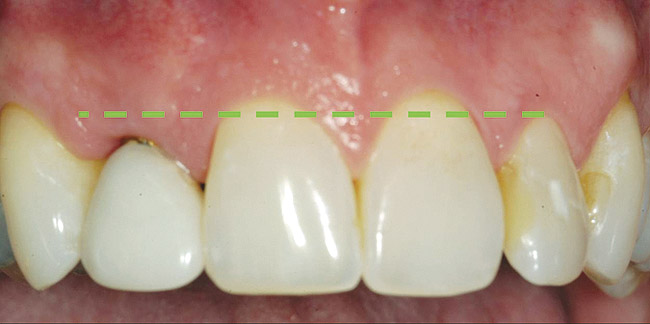

A 59-year-old woman presented with a recent history of trauma to her pre-maxilla, resulting in vertical root fracture of the maxillary left central incisor (Figure 1 and Figure 2). Examination revealed a mobile crown, moderate flat periodontal biotype, gingival margin of the left central incisor 1 mm coronal to that of the adjacent central incisor, central incisor tooth width discrepancy, and a medium smile line. The treatment plan included flapless extraction of the fractured tooth with the potential for simultaneous socket grafting using mineralized bone allograft (MinerOss®, BioHorizons, Inc, Birmingham, AL) and a free gingival graft (Figure 3) harvested from the left palate. Post-extraction examination revealed vertical labial plate loss of 2 mm and class I interproximal height of bone; therefore, all three procedures were performed. Four months postsurgery (Figure 4), a mid-crestal and sulcular incision without release was made to allow for crestal plasty and core biopsy (Figure 5). Histomorphometry revealed 87% vital bone with minimal evidence of residual allograft (Figure 6). This finding was consistent with type II bone density and allowed for non-submerged implant placement. The labial plate was completely regenerated. A provisional crown was placed and contoured to groom the soft tissue for 3 months (Figure 7), followed by final crown fabrication (Figure 8).

Figure 1  Frontal view of the failing maxillary left central incisor.

Figure 1

Figure 14  Immediate provisional crown in place, 2 months after implant placement surgery. Please note gingival margin height of opposing lateral incisor (dotted line).

Figure 14